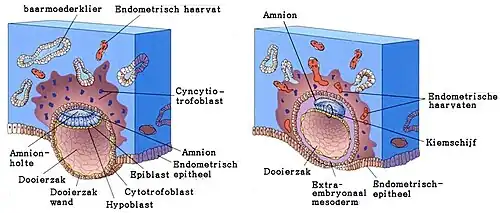

De ovulatie (eisprong) vindt gemiddeld twee weken na de eerste dag van een menstruatie plaats, als zwangerschap volgt dus bij een PML van twee weken. Binnen een etmaal daarna vindt dan de bevruchting (conceptie) plaats, waarbij een zaadcel een eicel bevrucht, waardoor er een zygote (bevruchte eicel) wordt gevormd. De zaadcel is over het algemeen afkomstig van een ejaculatie (zaadlozing) in de vagina bij vaginale geslachtsgemeenschap, niet meer dan drie etmalen voor de bevruchting. Circa zes dagen na de bevruchting volgt de innesteling, de nidatie van het embryo (de morula) in het baarmoederslijmvlies van de baarmoeder. Na een bevruchting blijven daaropvolgende menstruaties uit. Een zwangerschapstest is over het algemeen zinvol vanaf de dag dat de eerstvolgende menstruatie wordt verwacht: de test is, in het geval van zwangerschap, in het algemeen positief vanaf die dag of 1 à 2 dagen later. Eerder is de kans op een fout-negatieve uitslag groot.

Voor de innesteling deelt de zygote zich in kleinere cellen, een klompje totipotente (nog ongedifferentieerde) cellen dat zich excentrisch in de blastocyste bevindt. Circa zes dagen na de bevruchting, dus bij een PML van 3 weken, zijn er 16 tot 32 cellen en volgt de innesteling (nidatie) van het embryo (de morula) in het baarmoederslijmvlies (endometrium).